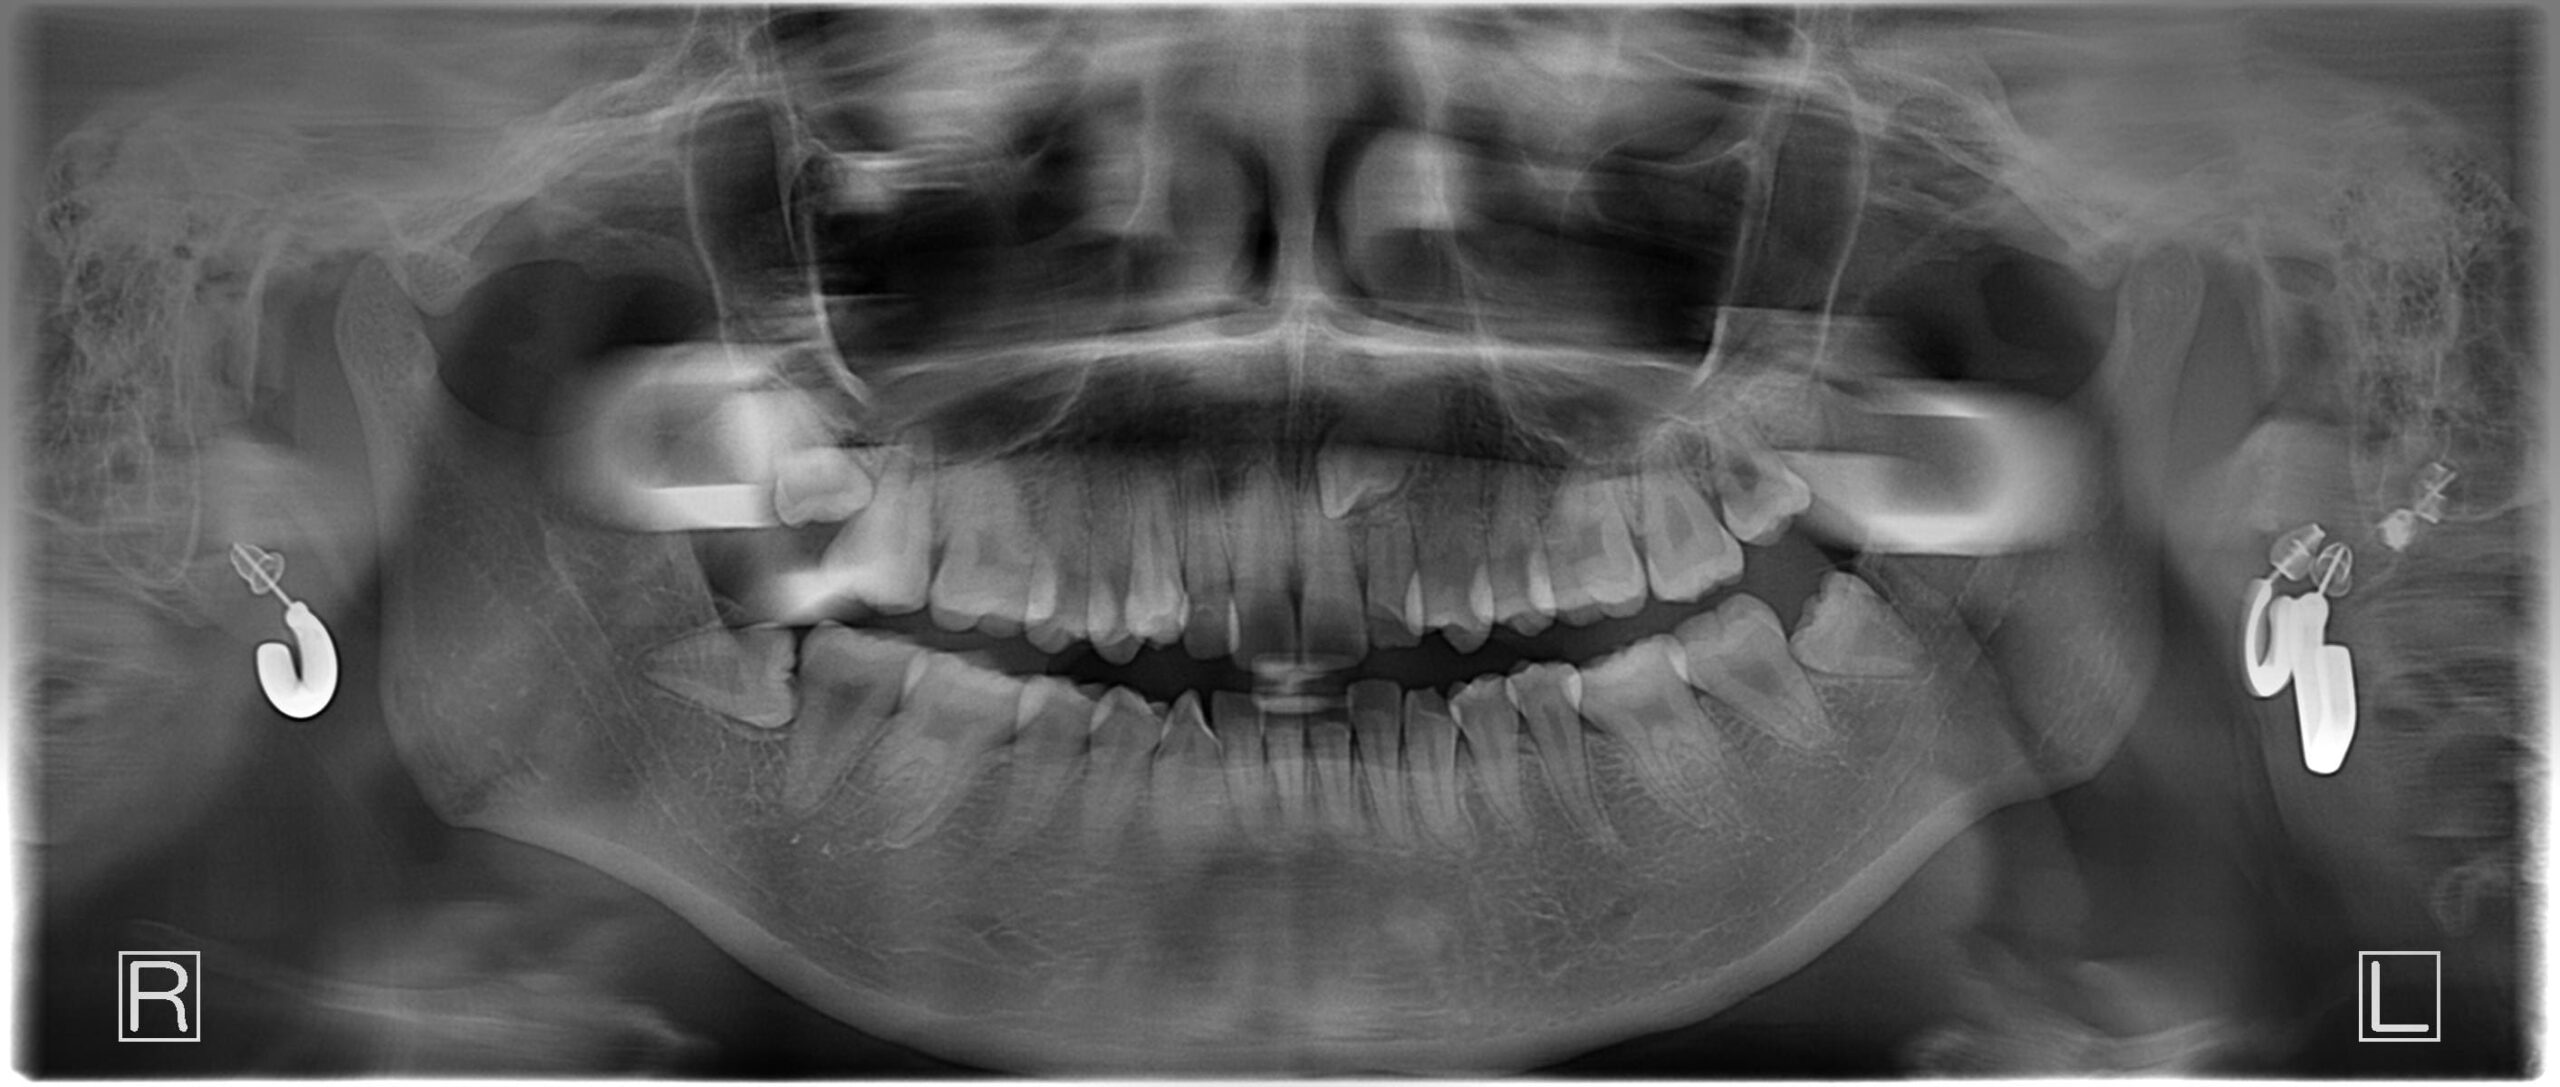

| 年齢・性別 | 21歳 |

|---|---|

| 主訴 | 叢生が気になる・前歯に埋伏歯がある |

| 治療期間・回数 | 6ヶ月 |

| 費用 | 935,000円 |

| 上顎の左側3番が埋伏していたため、上顎左右の3番および親知らずを抜歯し、矯正治療を行いました。 治療開始からおよそ6ヶ月で歯列が整い、審美的にも機能的にも良好な結果が得られた症例です。 |